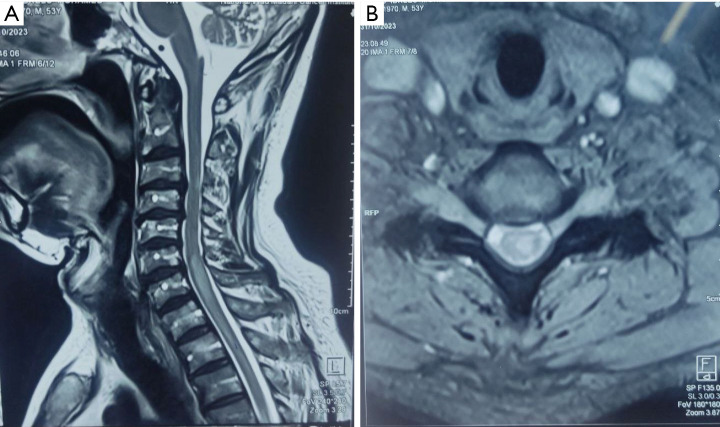

Case description: A 53-year-old hypertensive male, presented with subacute lower limbs weakness, sensory level below his nipples, and urine retention. Erythrocyte sedimentation rate (ESR) was above 112 mm/hour. Magnetic resonance imaging (MRI) spine showed a long segment of hyperintense signal seen on the T2-weighted image (T2WI) images in the spinal cord extending from C6 to D3 vertebral segments, with heterogeneous post-contrast enhancement. Cerebrospinal fluid (CSF) analysis showed lymphocytic pleocytosis with high protein and low glucose, and polymerase chain reaction (PCR) for Mycobacterium tuberculosis (MBTB) was positive. The patient received intravenous methylprednisolone daily for 5 days and standard anti-TB medications [rifampicin, isoniazid (INH), pyrazinamide, and ethambutol] for 12 months. However, repeated CSF analysis 3 months after starting anti-TB medications showed a negative PCR for MBTB, normal cell count, and glucose with slightly elevated protein. Still, the patient did not show any clinical improvement.